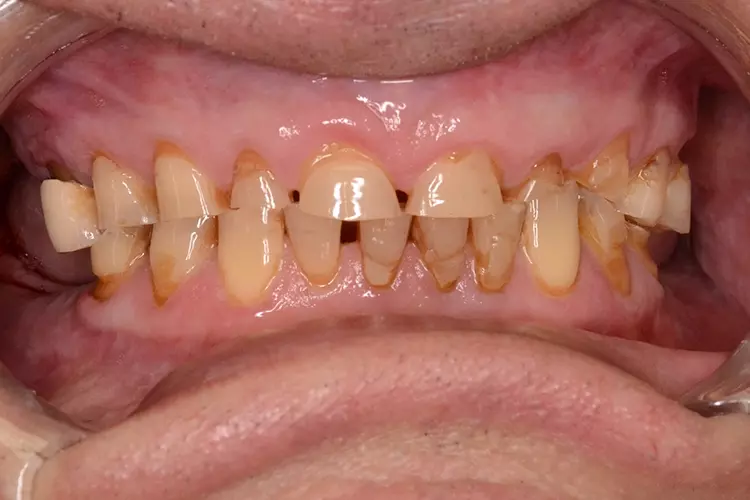

Bei dem heute 49-jährigen Patienten wurde seit Kindertagen versäumt, die Ober- und Unterkieferzahnbögen kieferorthopädisch auszurichten. Der Patient leidet seitdem stark unter seinen Zahnfehlstellungen.

Die Fraktur des stark elongierten Zahnes 21 war für den Patienten der Ausgangspunkt, sowohl die Front des Ober- als auch des Unterkiefers prothetisch überarbeiten zu lassen. Dabei wurde der frakturierte Zahn 21 durch ein navigiert eingesetztes Sofortimplantat ersetzt, während die verschachtelt stehenden Zähne 12 und 42 durch eine Brückenversorgung korrigiert wurden (Abb. 4a-j).